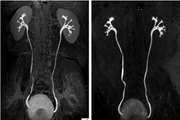

کرایوتراپی یا سرما درمانی، یک روش درمانی است که در آن از سرما برای درمان یا از بین بردن بافت های غیر طبیعی یا آسیب دیده استفاده می شود. این روش به طور معمول با استفاده از موادی مانند نیتروژن مایع یا گاز آرگون انجام می شود که دمای بسیار پایینی دارند و باعث انجماد و تخریب بافت های مورد نظر می شوند. کرایوتراپی چگونه کار می کند؟ در کرایوتراپی، بافت های غیر طبیعی یا آسیب دیده در معرض دمای بسیار پایین قرار می گیرند. این سرما باعث انجماد سلول ها و بافت ها شده و آنها را از بین می برد. در نتیجه، بافت های جدید و سالم می توانند جایگزین بافت های آسیب دیده شوند. کرایوتراپی می تواند برای درمان برخی از انواع سرطان ها مانند سرطان پروستات، سرطان کبد و ... استفاده شود.